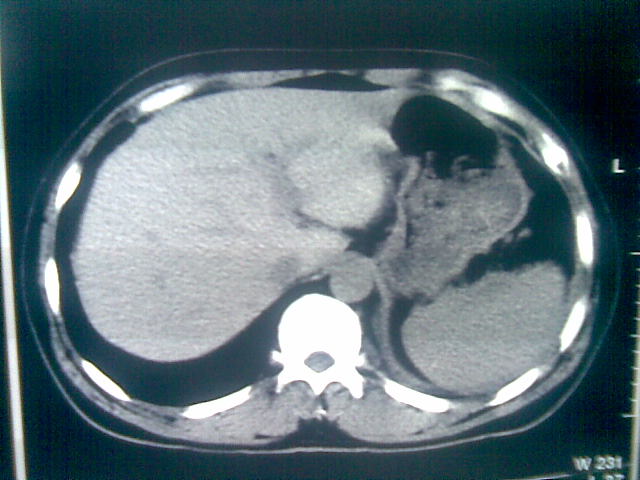

标题: CT23981:男,38岁阑尾炎术后透视胸腔积夜!做CT如下!积液包 [打印本页]

标题: CT23981:男,38岁阑尾炎术后透视胸腔积夜!做CT如下!积液包

可能与阑尾术后关系不太大,1.胸膜增厚粘连见少量气体。包裹脓气胸?左侧网膜囊脓肿?

.胸膜增厚粘连见少量气体。包裹脓气胸

左侧胸膜增厚、粘连+包裹液气胸。